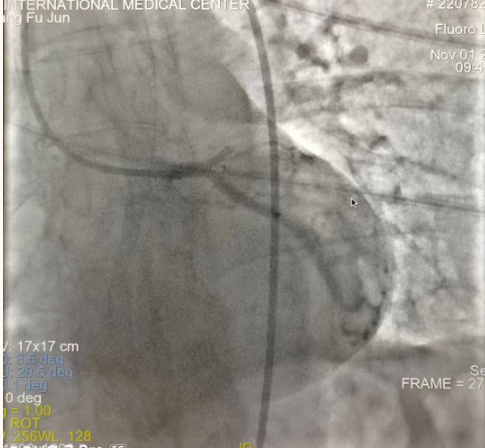

閉塞的血管再通時間取決于急救時長、轉(zhuǎn)運(yùn)時長和治療時長,在前兩方面,醫(yī)院已為患者爭取了最短時間?;颊呒覍龠h(yuǎn)在陜北,雖然已在趕來的路上,但最快抵達(dá)西安也要3小時,在與患者家屬電話溝通同意急診手術(shù)后,醫(yī)療總值班代家屬簽字,康曉軍在請示心臟病醫(yī)院王海昌院長及心臟內(nèi)科CCU尚福軍主任后,積極進(jìn)行術(shù)前準(zhǔn)備。在沒有家屬陪同、沒有交費(fèi)、沒有辦入院手續(xù)的情況下,患者經(jīng)胸痛中心綠色通道被送往心臟冠脈介入手術(shù)室,打通了完全閉塞的心臟前降支近段血管。